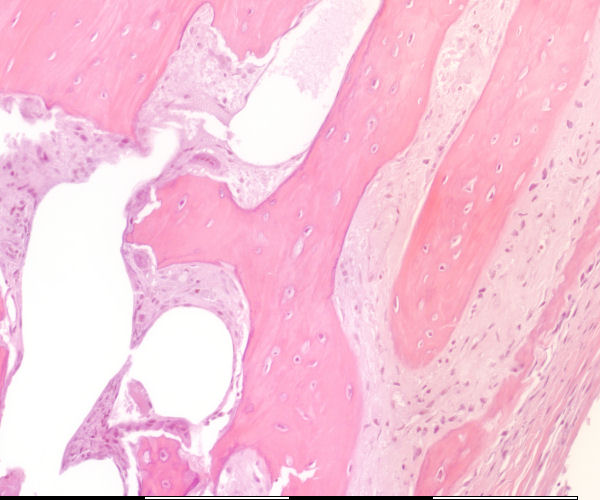

Medium magnification of immature bone

Groeilyne / Growth reversal lines Howship lakunae / Howship lacunae Lakunae / Lacunae Osteosiete in lakunae / Osteocytes in lacunae Endosteale selle / Endosteal cells Osteoblaste / Osteoblasts Osteoklast / Osteoclast